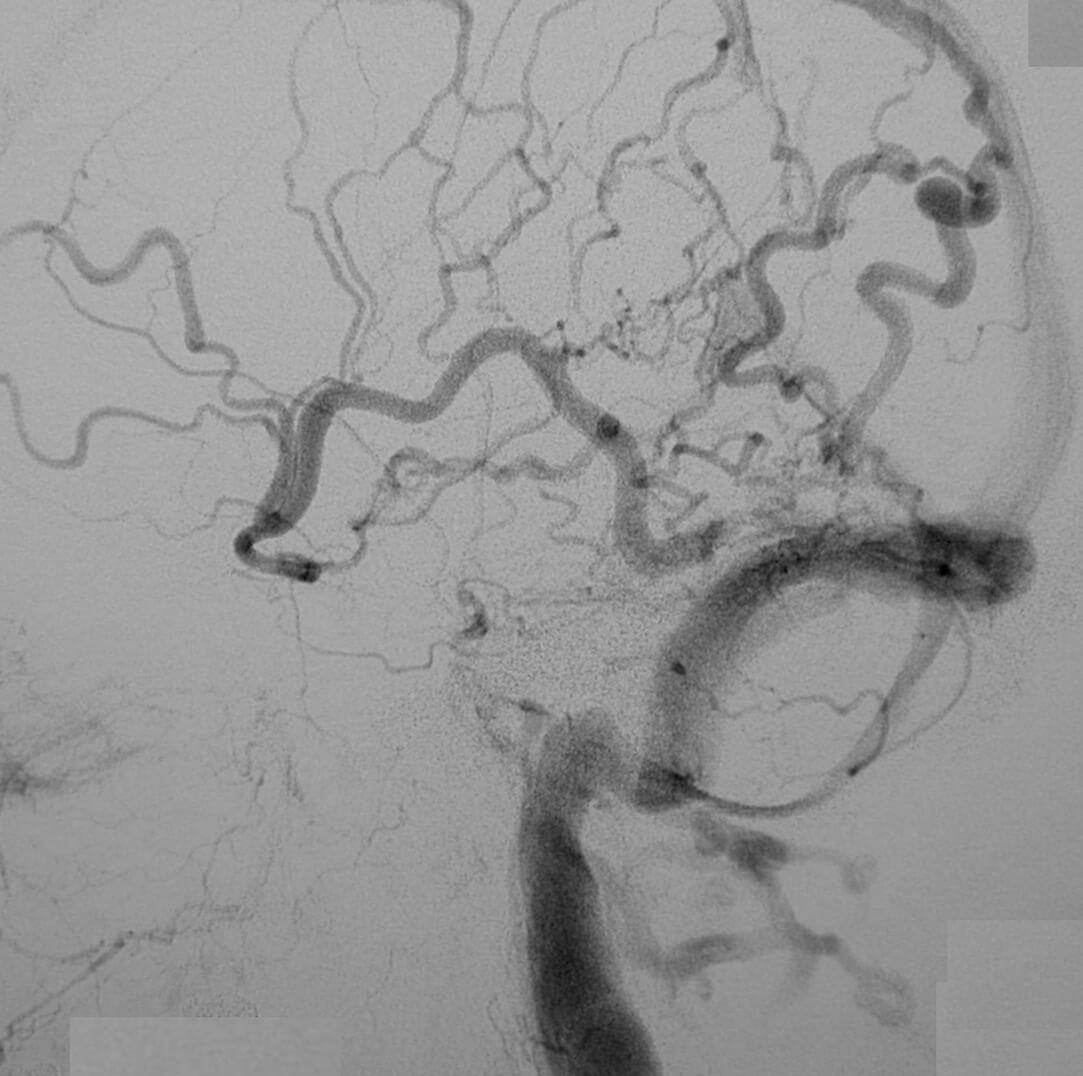

Η αξονική αγγειογραφία έχει ελαττωμένη ευαισθησία έναντι της μαγνητικής αγγειογραφίας.

Παρ´ όλα αυτά η συμβατική ενδαρτηριακή αγγειογραφία είναι η πιό ακριβής γιά την αναγνώριση αλλά και την κατηγοριοποίηση των ΑΦΔ της σκληράς μήνιγγας.